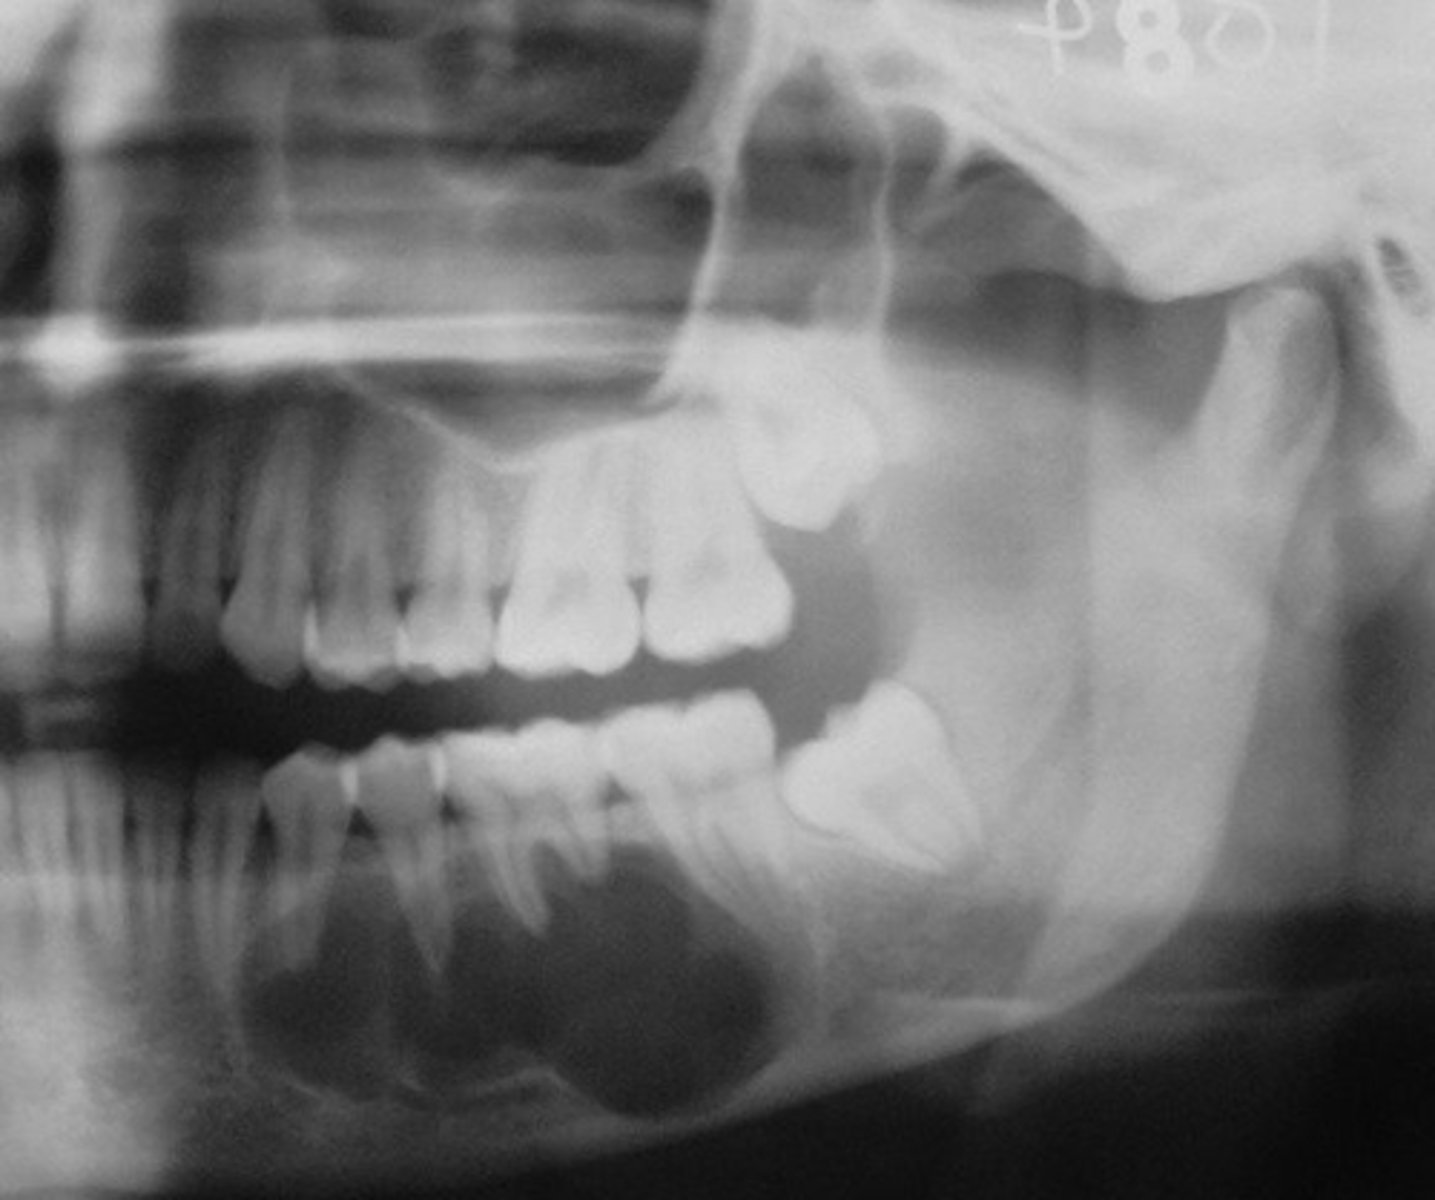

what is this?

what is this radiolucent area in the image?